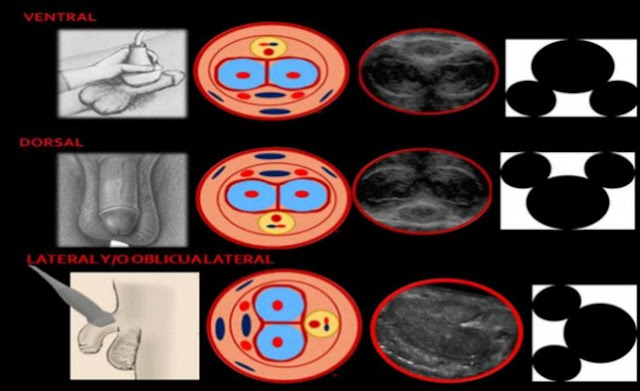

Realizar un Duplex peniano implica hacer una ecografía antes y después de aplicar una sustancia vasoactiva en el cuerpo cavernoso del pene, como vemos en la figura de arriba. La intención es ver cómo se comportan los vasos sanguíneos en el estado de flacidez y de erección, al suponer que el sujeto no tiene ninguna alteración, lo lógico es esperar que el flujo de sangre aumente al aplicar la sustancia; si esto no sucede posiblemente estemos ante una falla vascular, y estemos descubriendo la causa de la disfunción eréctil.

Leyenda imagen: Disposición de traductor con esquema y visión ecográfica. La colocación del transductor puede variar. En la primer columna (plomo) tenemos un gráfico del abordaje, en la segunda (rosado) el esquema donde se representan las estructuras anatómicas, en la tercera (gris oscuro) una imagen ecográfica, y la última (blanco y negro) imagen la figura símil Mickey que nos recuerda de una manera práctica donde se ubican los cuerpos cavernosos con respecto al esponjoso en cada exploración. En la primer hilera tenemos la exploración ventral clásica, y luego las dos opcionales dorsal y laterales.